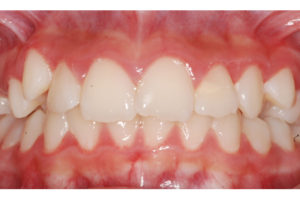

Documento utilizado en todo procedimiento odontológico y en cualquier especialidad, consiste en una secuencia de fotos faciales y dentales en diferentes ángulos, que permiten un diagnostico ideal y evaluar los avances del tratamiento al tener fotos posteriores, además es un documento legal.